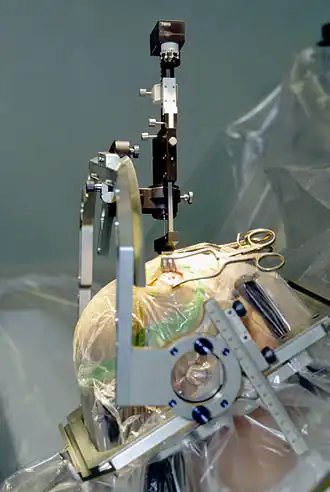

DBS leads are placed in the brain according to the specific symptoms to be addresses and implantation may take place under local or general anesthesia. A hole about 14 mm in diameter is drilled in the skull and the probe electrode is inserted stereotactically, using either frame-based or frameless stereotaxis.[22] During the awake procedure with local anesthesia, feedback from the individual is used to determine the optimal placement of the permanent electrode. During the asleep procedure, intraoperative MRI is used to image the brain during device placement.[23] The installation of the IPG and extension leads occurs under general anesthesia.[24]